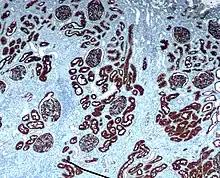

CD10 immunohistochemical staining of normal kidney. CD10 stains the proximal convoluted tubules and glomeruli.